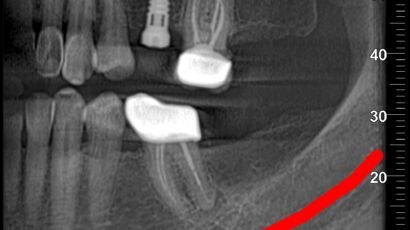

El Tac dental maxilar, también conocido como tomografía computarizada de haz cónico (CBCT, por…